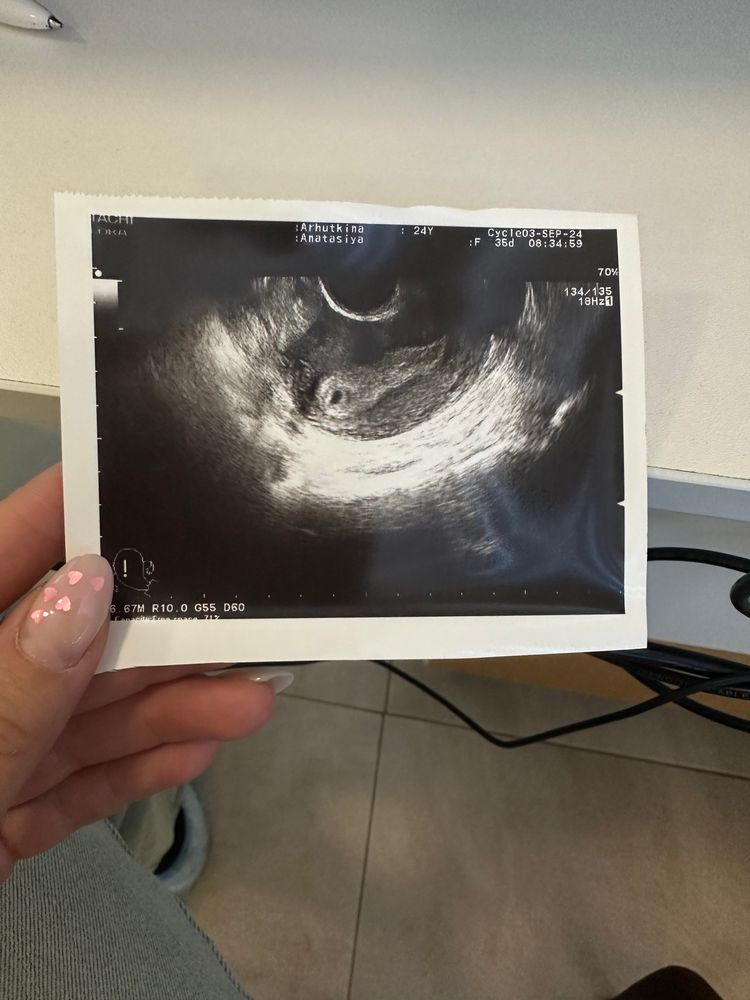

Первое узи 5 недель после месячных

Алена Кос, сегодня получается 4 недели и 6 дней,вчера хгч был 1260 в 8 утра,сначала не увидела пя гинеколог,я испугалась,а потом вот…🤞😀

Алена Кос, нет,овуляция была на 17 дц,первое узи на 18 дпо